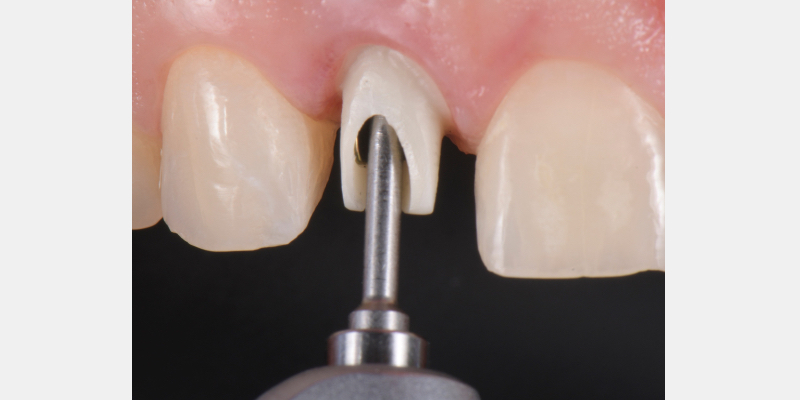

Here is a simple, step-by-step technique for fabricating a silicone jig to avoid excess cement in a cement-retained implant-supported restoration. It can be applied to a single crown or to an implant-supported cement-retained bridge.